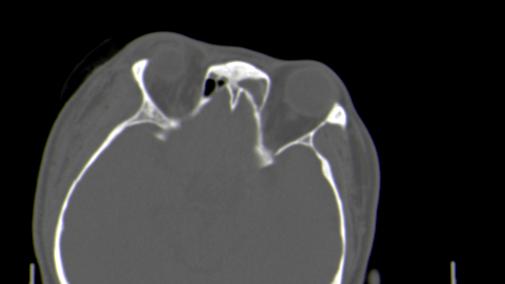

以下是引用皎皎白驹在2006-11-29 8:48:00的发言:[br]影像表现:双侧筛窦和上颌窦、鼻腔内均密度增高,右侧视神经增粗、弯曲,左筛窦顶部筛板及右侧纸板近视神经孔区可见骨折线。[br]结合临床表现考虑:右侧筛窦纸板近视神经孔区骨折致右侧视神经损伤。最好做个眼眶冠状扫描,更明确右侧视神经管是否狭窄。

以下是引用w_jianhua在2006-11-29 10:07:00的发言:[br]影像表现:双侧筛窦和上颌窦、鼻腔内均密度增高,右侧视神经增粗、弯曲,左筛窦顶部筛板及右侧纸板近视神经孔区可见骨折线。[br]结合临床表现考虑:右侧筛窦纸板近视神经孔区骨折致右侧视神经损伤。最好做个眼眶冠状扫描,更明确右侧视神经管是否狭窄。 [br] [br]支持[br]